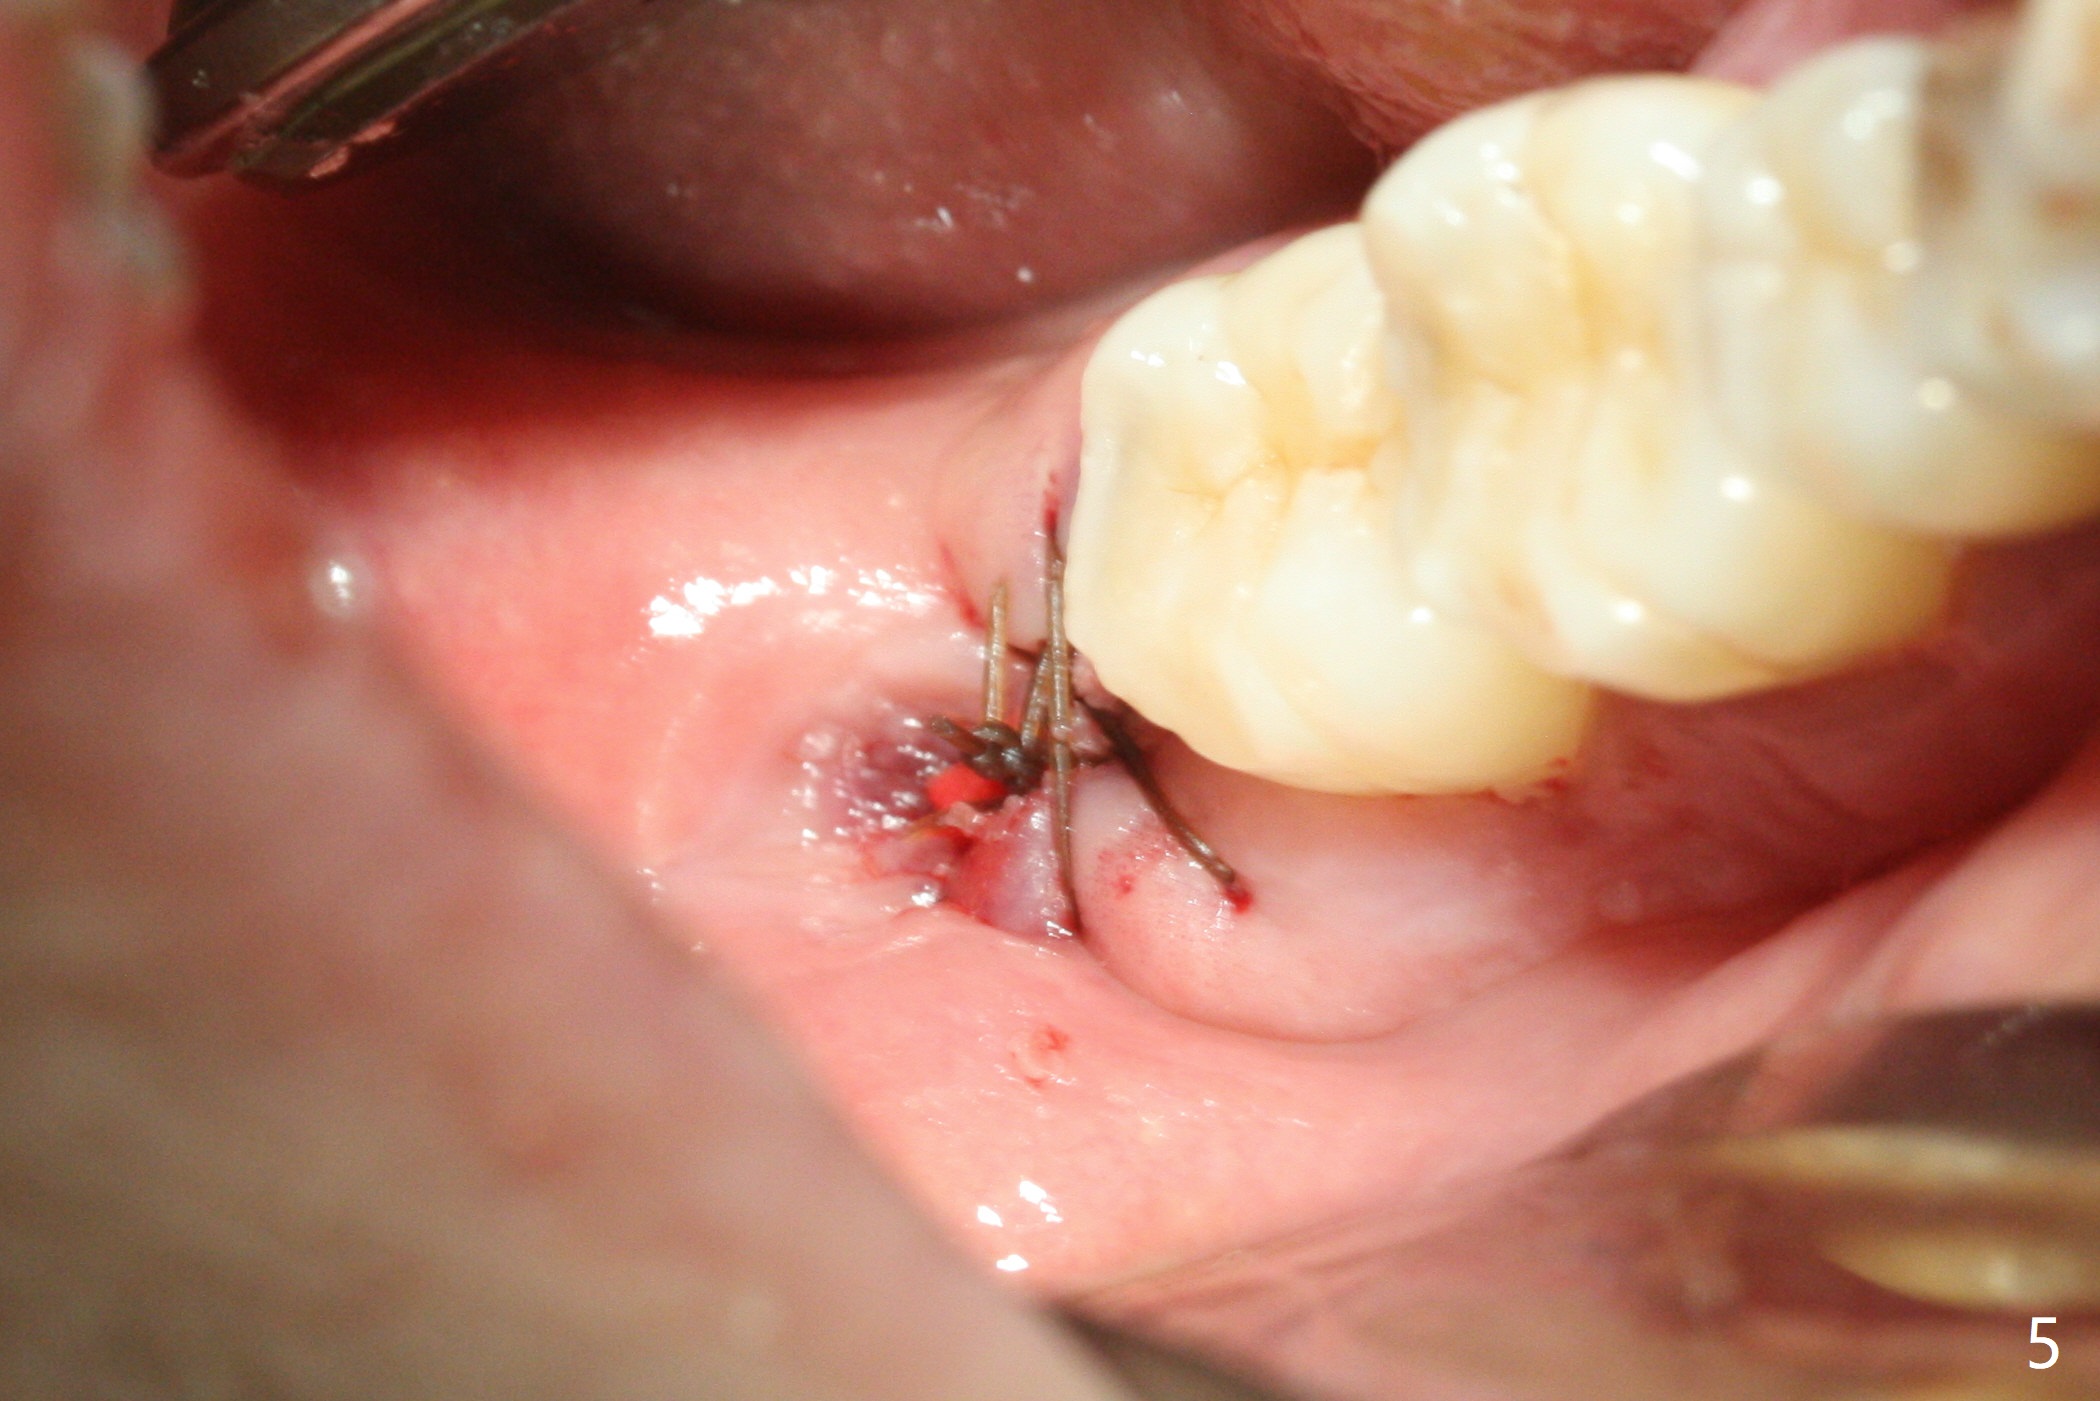

with Severe Bone Loss

A 44-year-old woman (YHM) has generalized moderate localized severe chronic periodontitis (Fig.1). Periodontal abscess develops between the teeth #31 and 32. Since the pain and mobility is more severe at #32 than 31, the former is extracted (Fig.2). After thorough curettage and copious irrigation, Osteogen plug is placed in the distal portion of the socket (Fig.3, 4 O), while allograft in the mesial one (B), with collagen plug on the top (C) before suturing (Fig.5). The tooth #31 is stable and pain-free with formation of new bone distal 7 months postop (Fig.6,6' *), while bone loss at #3 and 4 is more severe.